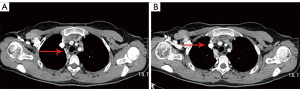

Tumor resection was performed in August 2018. Pleural adhesion was observed during the operation. The tumor was located in the right middle and superior mediastinum. Cystic fluid pushed outward, oppressing the deep part of the azygos vein arch and superior vena cava. The tumor reached below the right internal jugular vein, the inferior pole was located below the azygos vein arch to the hilum of the lung, and the inside the edge of the tumor reached the right internal mammary vein. The tumor surrounded the superior vena cava, phrenic nerve and azygos venous arch, and its lower part adhered severely to the hilum of the lung, the deep part of the pericardium, and the anterior mediastinum. As bleeding occurred several times during the surgery, and it was difficult to separate the tumor from normal tissues, we resected the tumor by dividing it into three parts. The first part of tumor was the triangular area formed by the superior vena cava, the azygos vein arch, and the right innominate vein. The second part was from the left side of the superior vena cava to the left edge of the tumor. The third part was from the deep part of the superior vena cava to the lower pole of the tumor. During the operation, the integrity of the tumor was destroyed as much as possible, and the surrounding nerves and blood vessels were protected (see Video S1). The postoperative pathology results confirmed a mediastinal mature cystic teratoma (see Figure 2). 1 year later, the chest CT showed that the residual tissue had been absorbed, and the blood vessels were largely restored and had healed well (see Figure 3).